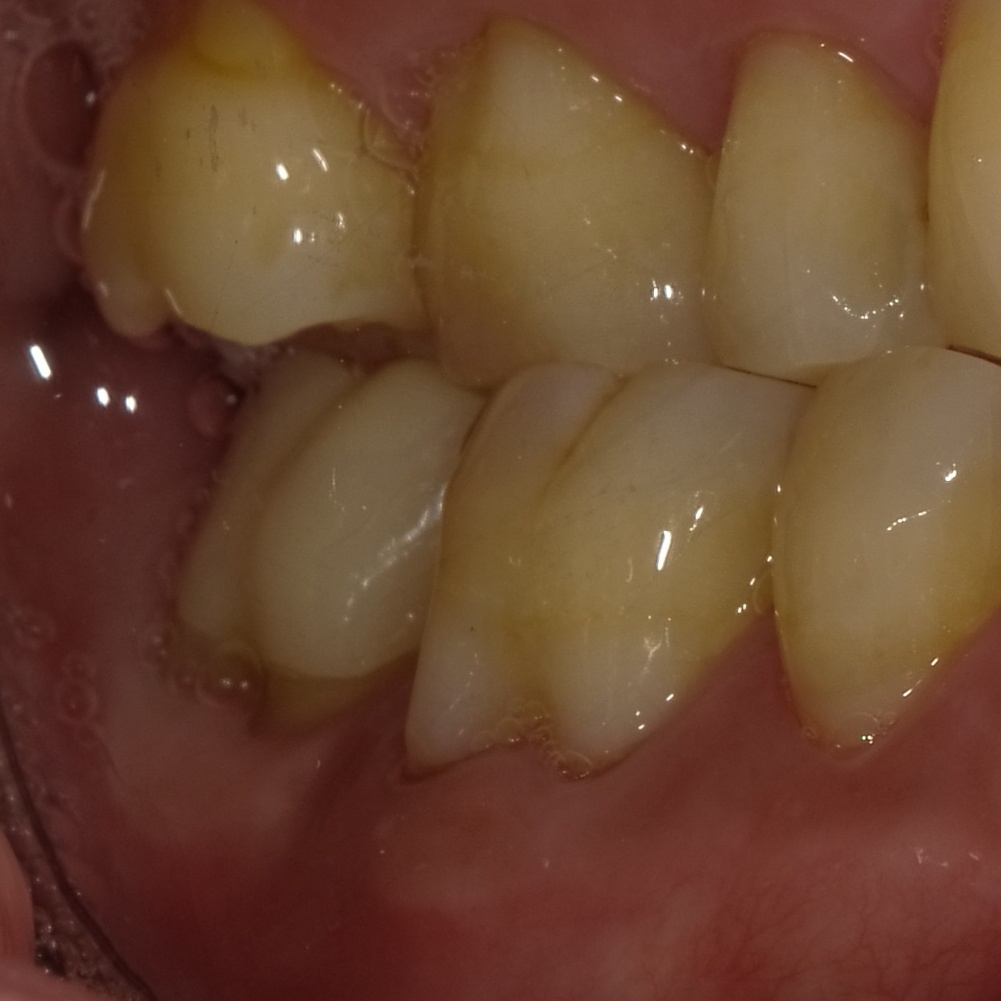

治療後3ヶ月、歯茎のできものは消えています。この時点で治癒傾向が確認され、最終的な被せを進めていきます。

治療後1年の歯肉。歯茎は健康な状態へと回復しています。